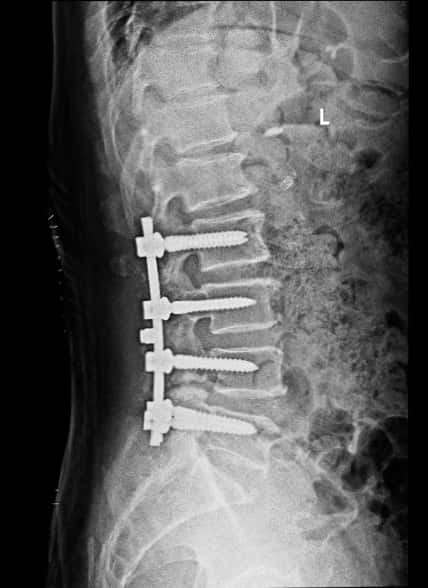

腰椎术后侧位片

手术顺利,麻醉师功不可没!整个减压内固定的时间1小时23分钟,手术中出血约200毫升,出血回吸收122毫升。手术后右下肢疼痛消失,术后第四天下地行走,双下肢活动正常。术后两周一切平稳,没有出现高血压,心脏病相关的并发症。